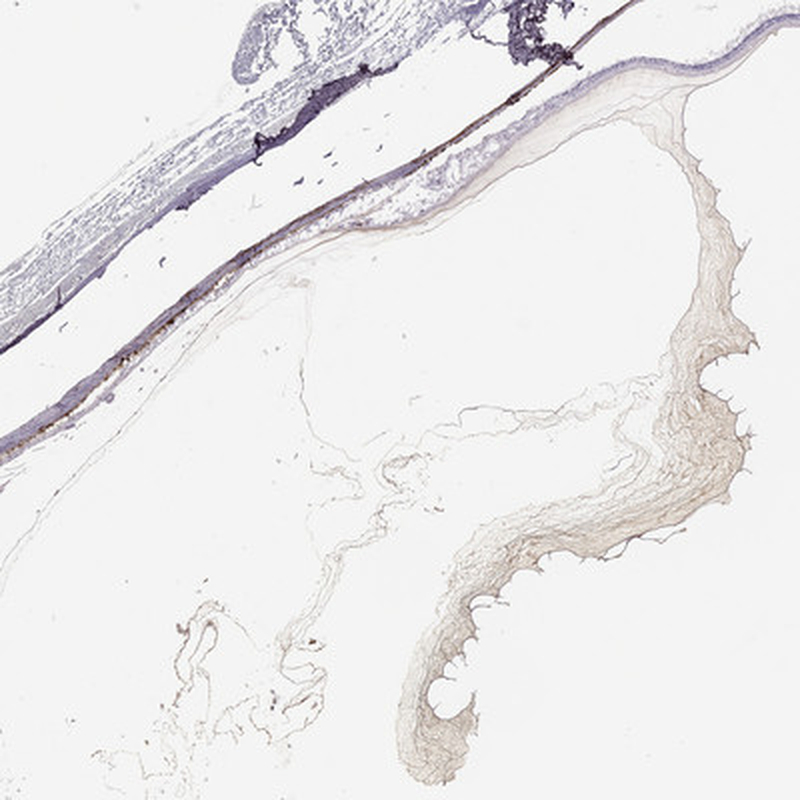

Immunohistochemical staining of human eye shows strong staining in positivity in vitreous humor.